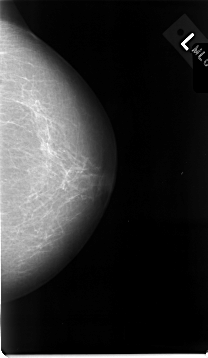

C_0014_1.LEFT_CC

LEFT_CC LINES 4648 PIXELS_PER_LINE 2696 BITS_PER_PIXEL 12 RESOLUTION 50 NON_OVERLAY

LEFT_MLO LINES 4632 PIXELS_PER_LINE 2824 BITS_PER_PIXEL 12 RESOLUTION 50 NON_OVERLAY